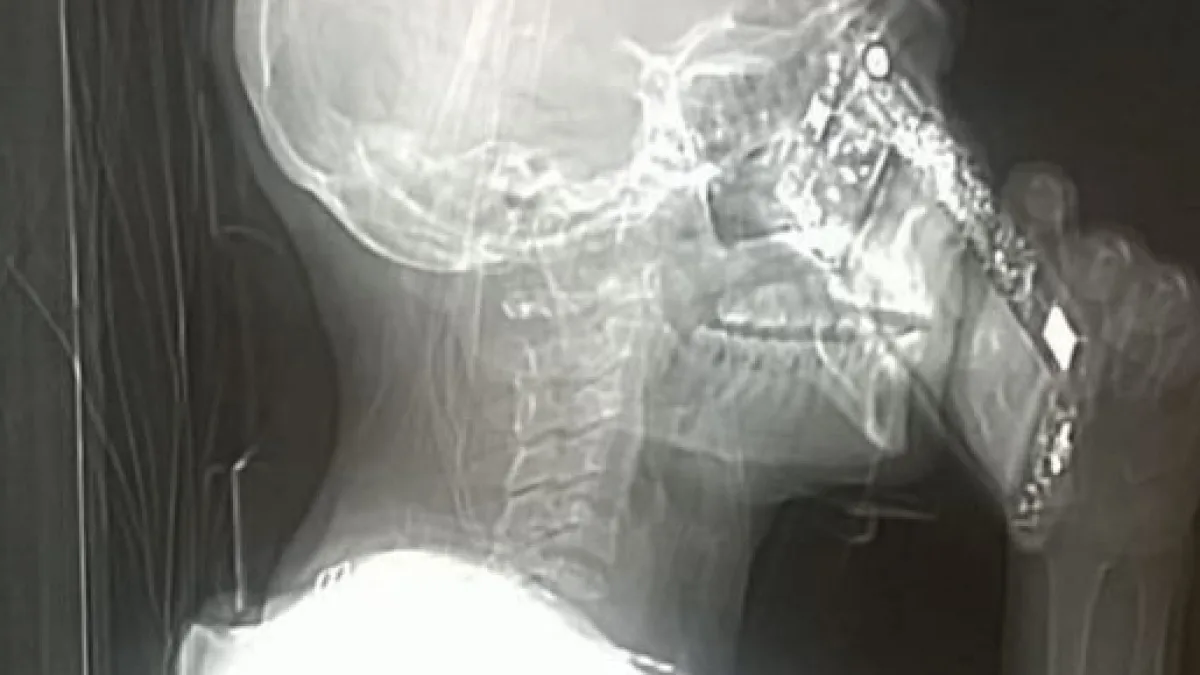

Dimenticanza o dipendenza, il risultato è stato fantascientifico: la signora che nel corso della Tac ha risposto al telefono, ha dato vita ad un'immagine che sta impazzando sui social. Pare una cyber-donna, con un telefono che sta diventando parte di lei a tutti gli effetti. Anche se la signora si è giustificata dicendo di essere stata una dimenticanza.